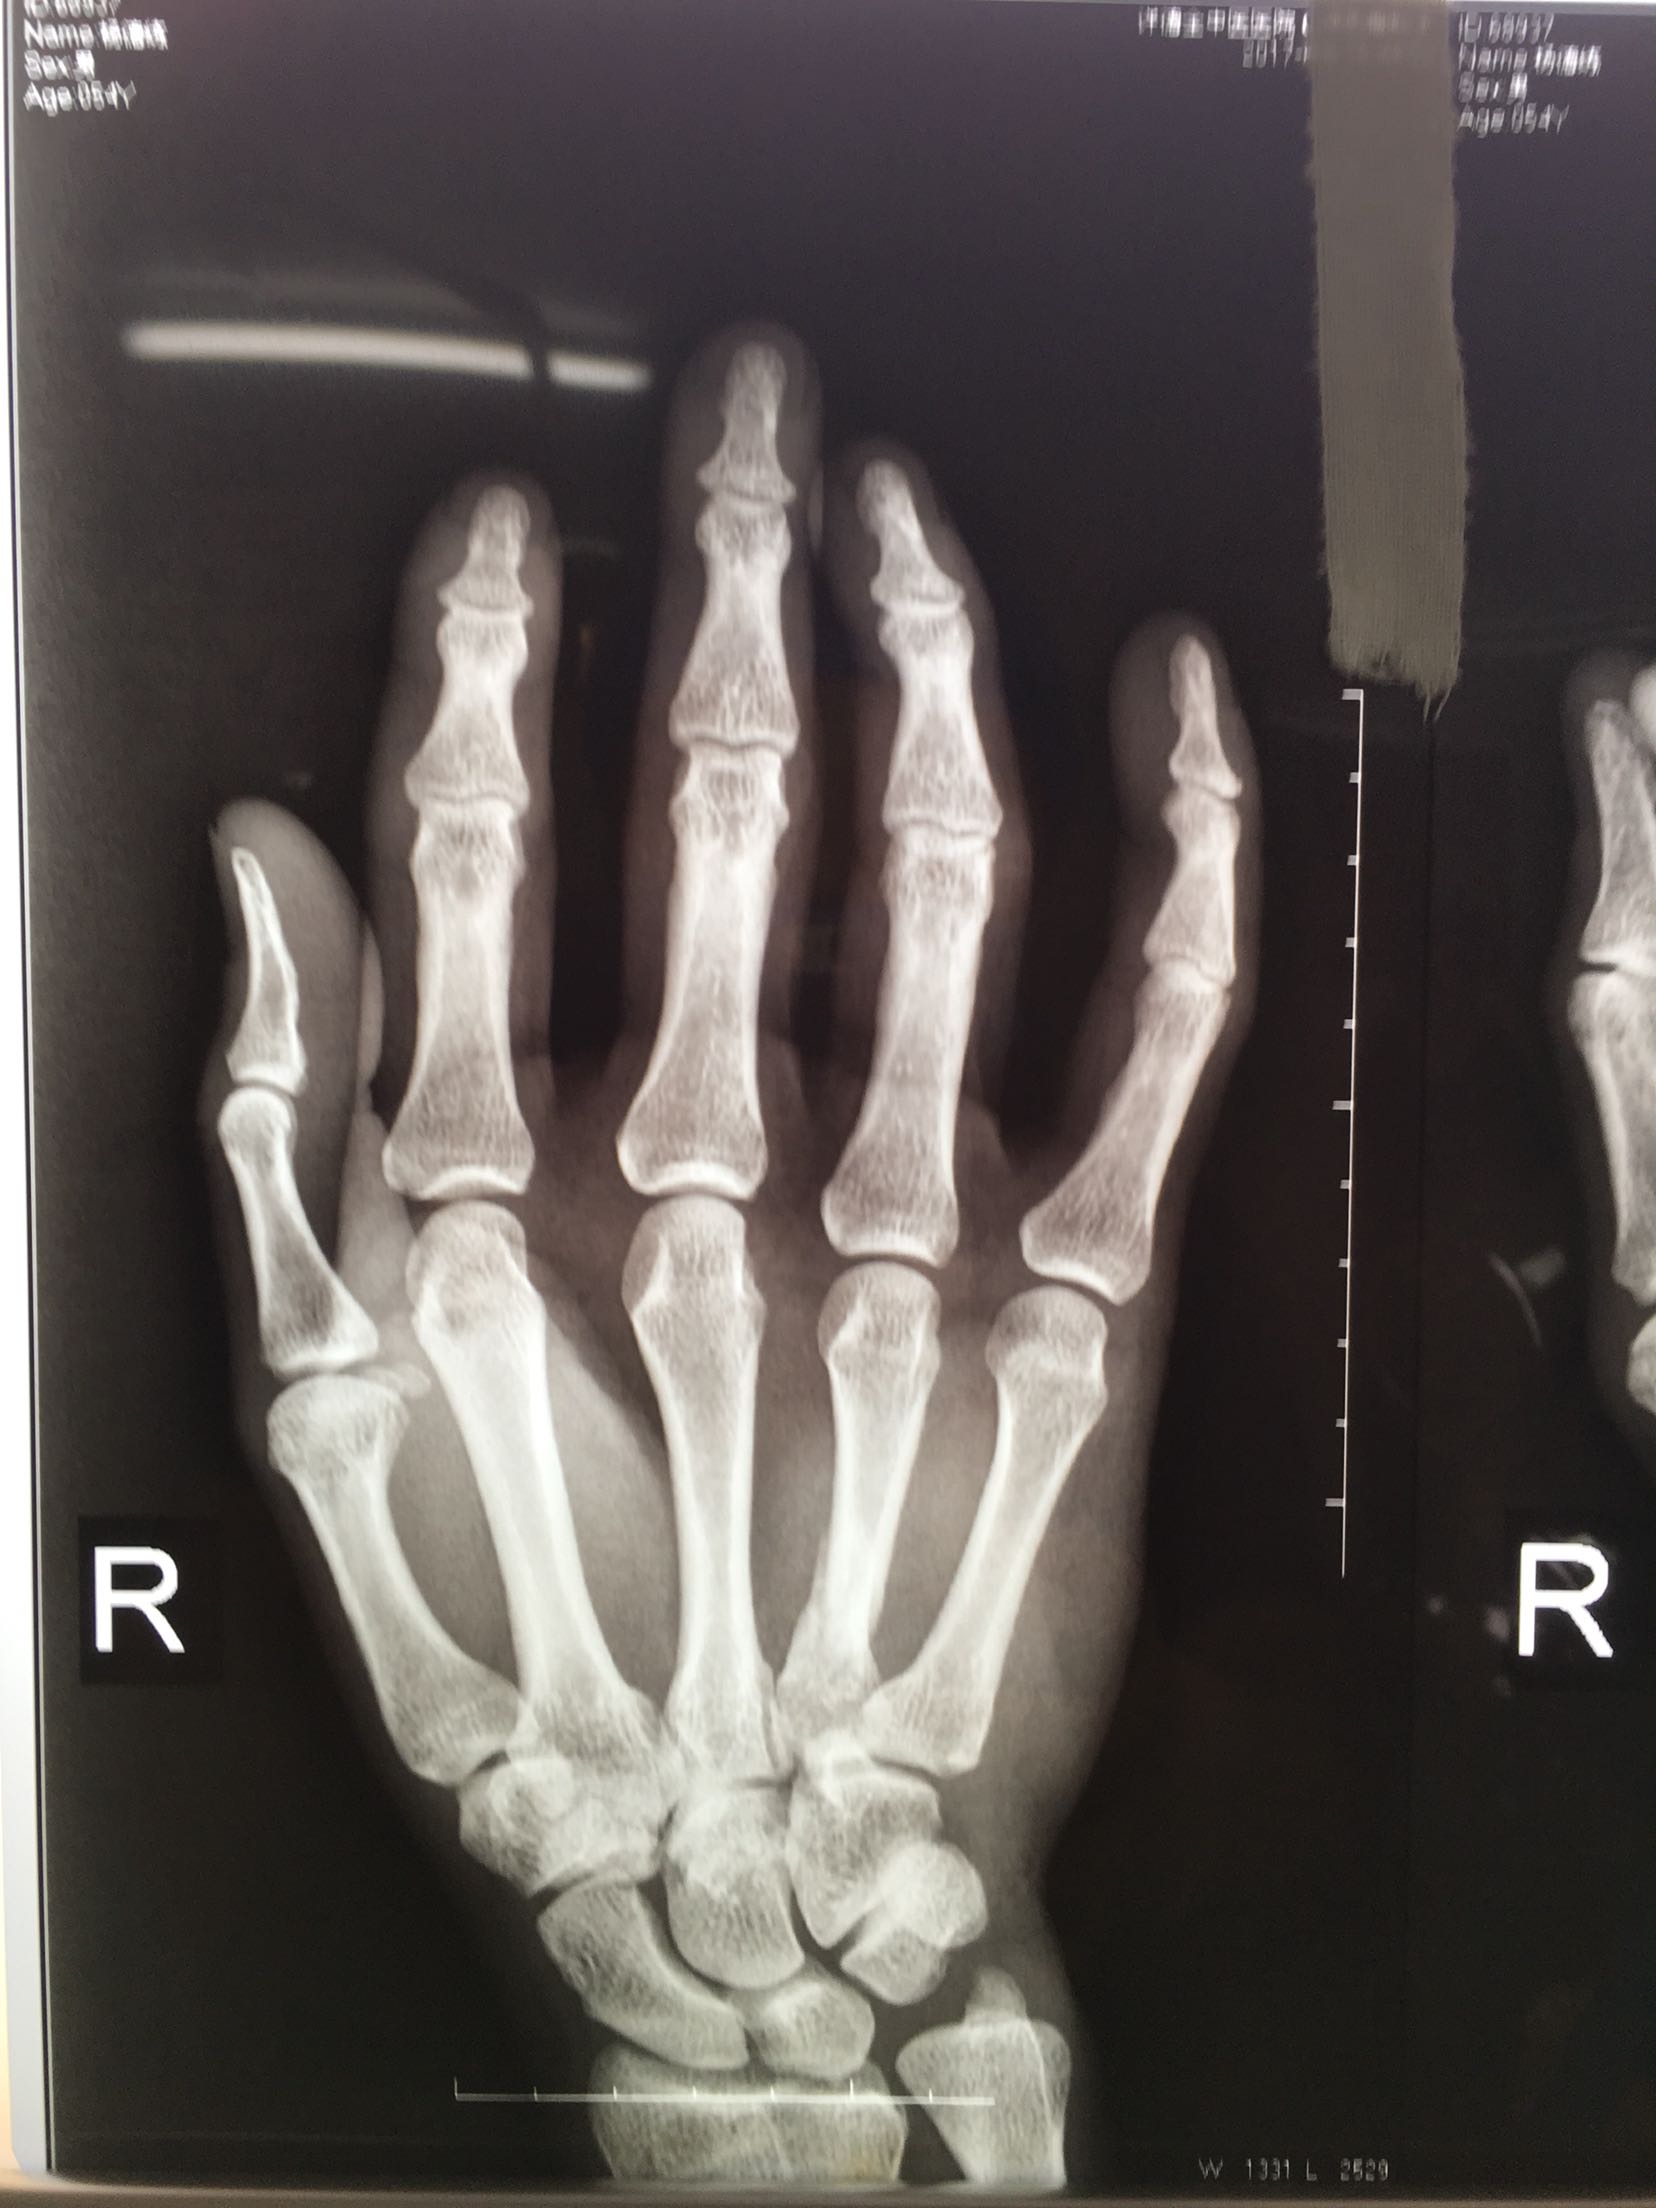

患者,男,52岁,摔伤后右手肿痛,活动受限4小时入院。

右手掌肿胀明显,皮色皮温正常,局部压痛,纵叩痛阳性,可及骨擦感,第四掌指关节活动受限,末梢血运感觉正常。

完善检查,在臂丛麻醉下行切复内固定术,术后抗炎,消肿止痛处理。